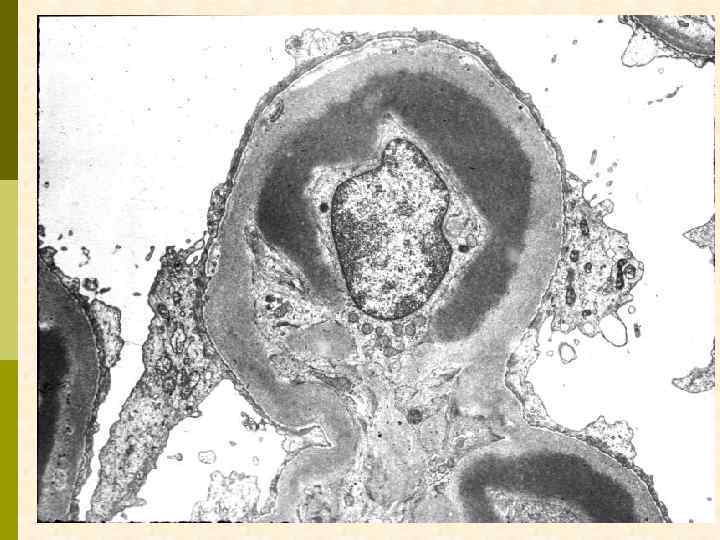

ХРОНИЧЕСКАЯ ТРОМБОТИЧЕСКАЯ МИКРОАНГИОПАТИЯ Ранние признаки: набухание эндотелиоцитов, потеря фенестр, отделение эндотелия от мембраны, заполнение субэндотелия электронно-прозрачным материалом (белки, участвующие в процессе свертывания + клеточный детрит), новообразование базальных мембран под смещенным эндотелием. Нефробиоптат больного первичным антифосфолипидным синдромом

ХРОНИЧЕСКАЯ ТРОМБОТИЧЕСКАЯ МИКРОАНГИОПАТИЯ Удвоение базальных мембран при световой микроскопии, сегментарный склероз. Ремоделирование капиллярной стенки при разрешении острого эпизода или при хронической тромбофилии создает маску иммунокомплексного МПГН. Нефробиоптат больного первичным антифосфолипидным синдромом